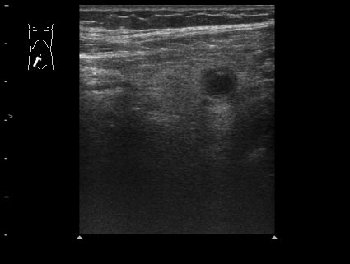

Пациент 32 лет.

В правой подвздошной области определяется утолщенный аппендикс, не компрессируется при надавливании датчиком, в просвете определяется аппендиколит; окружающие аппендикс ткани инфильтрированы.